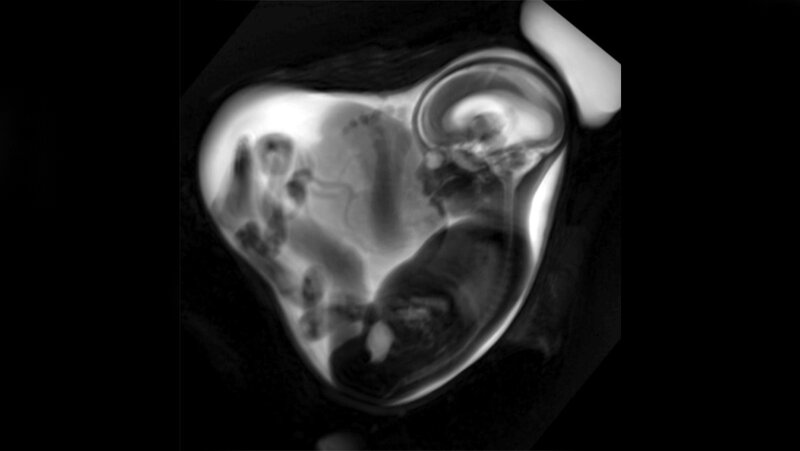

Diese Reduktion des Lungenvolumens war laut Studie besonders deutlich, wenn die Infektion im letzten Drittel der Schwangerschaft stattgefunden hatte. Die Daten wurden erhoben, bevor eine Impfung gegen SARS-CoV-2 verfügbar war. Die Forscherinnen und Forscher um Prof. Dr. Sophia Stöcklein von der Klinik und Poliklinik für Radiologie des LMU Klinikums und Privat-Dozentin Dr. Anne Hilgendorff vom Zentrum für Comprehensive Developmental Care des LMU Klinikums und von Helmholtz Munich haben insgesamt 34 Schwangere respektive Feten mittels fetaler MRT untersucht. Die fetale MRT ist eine hochspezialisierte Untersuchungsmethode, die es ermöglicht, die Entwicklung fetaler Strukturen bereits vor Geburt detailliert zu untersuchen. Die Frauen hatten sich zu unterschiedlichen Zeitpunkten mit der Alpha-Variante des Coronavirus infiziert, bestätigt durch PCR-Test. Die Lungen der Feten wurden mittels Magnetresonanztomografie vermessen, das Lungenvolumen bestimmt und mit Feten aus einer sogenannten Referenzkohorte verglichen, bei denen keine Infektion während der Schwangerschaft stattgefunden hatte.

„Die Feten von Schwangeren, die positiv auf SARS-CoV-2 getestet waren, hatten insgesamt ein im Vergleich zur Referenzkohorte geringeres Lungenvolumen“, erklärt Sophia Stöcklein. Bei den Feten im dritten Trimenon war der Effekt besonders deutlich, mit durchschnittlich 69 Prozent des zu erwartenden Durchschnittswerts bei normaler Lungenentwicklung.

Eine mögliche Erklärung für dieses Phänomen könnte der Transfer des Virus über die Plazenta in das Fruchtwasser und von dort in die fetale Lunge sein. „Dabei ist das dritte Trimenon in der Lungenentwicklung besonders durch die Reifung wichtiger Zellen an der Gasaustauschfläche gekennzeichnet“, erklärt Anne Hilgendorff, „sodass ein Kontakt dieser Zellen mit dem Virus eine Veränderung der Lungenentwicklung bedingen könnte.“